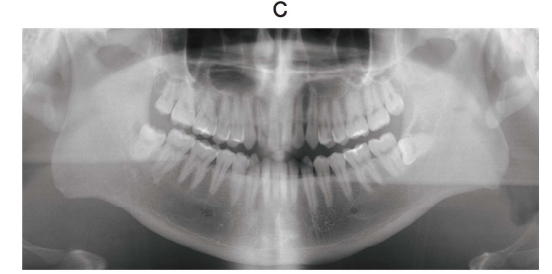

21 歳の男性。下顎右側智歯部の疼痛と腫脹を主訴として来院した。 3 日前から右側顎下部に腫脹が出現し、徐々に拡大し嚥下痛が強くなり、飲水ができないという。体温は 37.8℃、腫脹部は弾性硬で、開口量は 20 mm、呼吸障害は認めない。初診時の顔貌写真(別冊No. 3A)、口腔内写真(別冊No. 3B)、エックス線画像(別冊No. 3C)及び造影 CT(別冊No. 3D)を別に示す。

まず行うべき処置はどれか。 2 つ選べ。

解答:a d

解説:

「まず」と聞かれていることに注目!急性症状を抑えてあげよう。

水が飲めない⇒脱水の危険性がある⇒輸液で水分を補給してあげる

dかeで迷う。写真Bより排膿しているのでeまでしなくてよい。疼痛、腫脹、発熱より感染が疑われるのでdの抗菌薬投与を選ぶ。